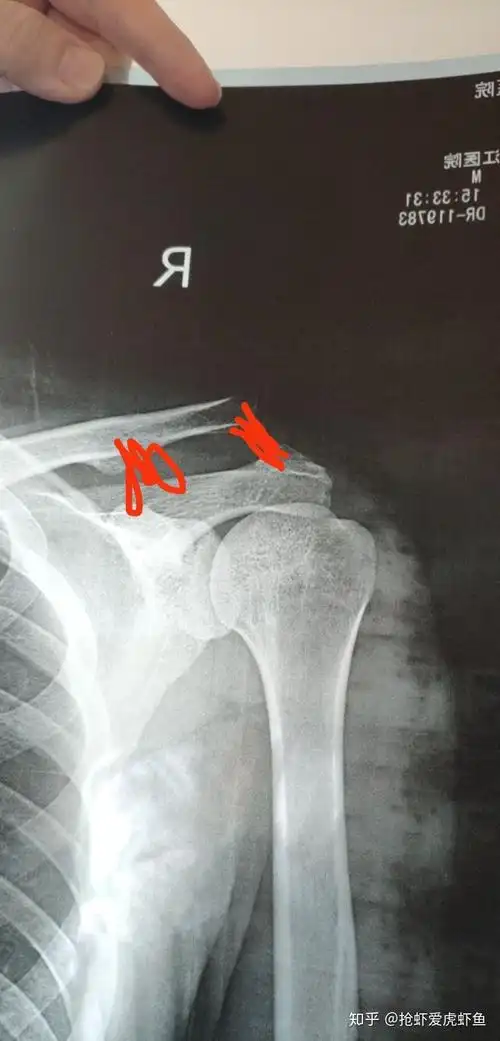

肩锁关节脱位不需戴钢板这个微创手术只留几个小眼